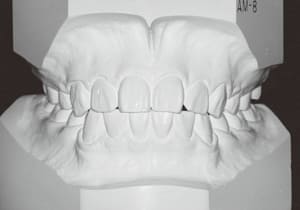

2 After Phase 2 Treatment 6-6-’94

The first phase of treatment involved extracting the left and right maxillary deciduous canines. The space created was used to forcibly retract the four anterior teeth, thereby aiming to improve lip closure function (6–9, 11). Morphological changes suggest that lip function differed before and after treatment (6, 9). Subsequently, the first premolars erupted, but extraction is planned to secure space for canine eruption (10). A Class II molar relationship remains, but the significant overjet has improved (11).

In the maxilla, insufficient space for canine eruption was inevitable, necessitating extraction as part of the treatment plan. The maxillary first premolars on both sides were extracted during routine observation to create space for canine eruption (14). Eventually, the canines erupted and settled into relatively favorable positions (15,19,20). In the mandibular dentition, crowding was also present, leading to extraction of the mandibular first premolars on both sides. Treatment with full bracket was then initiated (17).